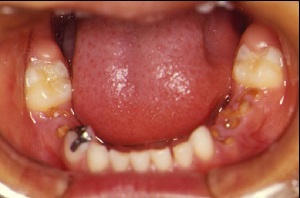

現在、モンゴルの首都ウランバートルでは、乳歯う蝕の洪水ともいえる時代を迎えている。

モンゴル4歳児の1人平均dmf歯数は9.25歯であるが、これはわが国で最も高かった昭和38年(1963年)の8.5歯よりさらに多い。

そこでモンゴルでの歯学教育の一環として、子ども達の現状を知らせることが先決だと思い、口腔内写真を撮影しう蝕の実態を提示した。

(図1)